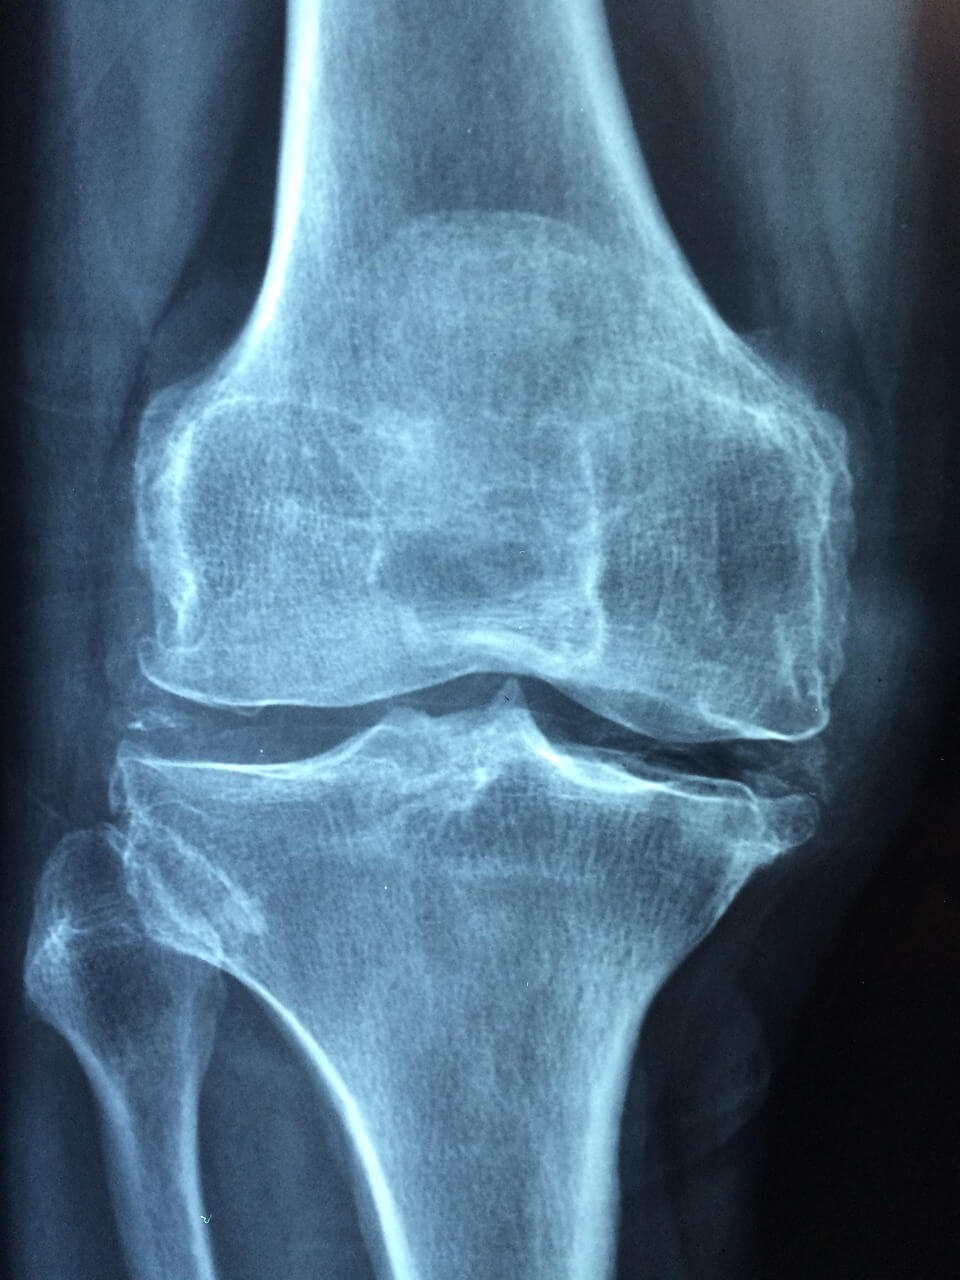

- 이중에너지 X선 흡수계측(DEXA): 골밀도 표준

- 필요 시 척추 단순 촬영(압박골절 확인)